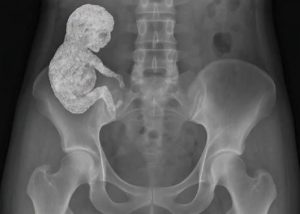

Kada je zena od 82 godine osjetila jake bolove u donjem dijelu stomaka prva pomisao je bila da se ona suocava sa necim jako ozbiljnim a to da je neko tesko boljenje. U tom periodu svaki simptom izvan uobicajnih zdrastevnih problema moze da dovede do panike i straha. Ona je brzo odvedena u bolnicu gdje je medicinski tim poceo da radi na njoj detaljnu dijagnostiku. Ono sto su oktirli nije bila potvrda na tesko oboljenje nego je slucaj koji je sokirao zada ljekare ali i javnost. Ovo je slucaj koji se postavio kao medicinski fenomen kao i svjedocanstvno kako se ljudsko tijelo treba da bori. Umjesto tog tumora koji se ocekivao u njenom tijelu je pronadjen kalcificiran fetus koji je bio star vise od 40 godina. Ovo je fenomen poznat kao litopedion ili kamena beba i jako je rijetko u medicinskoj literaturi i zabiljezen je samo nekoliko puta. Iza ove price se krije prica o jednoj vanmatericnoj trudnoci o kojoj zena pojma nije imala ali je trajala toliko godina.

Litopedion se javlja kada se plod pocne razvijati van maternice a to je u trbusnoj supljini. U ovim situacijama ako trudnoca nije prekinuta na vrijeme moze doci do velikih problema. U ovom slucaju zenin organizam je prepoznao fetuus kao strano tijelo koje ne moze da izbaci te je ga oblozio kalcijem i to je tao zastitio tijelo od nekih infekcija. Na taj nacin fetus je postao kamen i ostao je neprimjecen skoro pola vijeka. Nevjerovatna je spsobonost ljudskog tijela da se adaptira i da nadje nacin da se bori protiv necega sto se smatra stranom supstancom. Citavo to vrijeme zena nije imala neke simptome i sve do trenutka kada nisu krenuli bolovi i to radi pritiska kalcifikata na druge organe. u razgovoru sa ljekarima vjerovala je da je imala spontanio pobacaj prije mnogo godina ali istina je daleko od toga. Operacija se desila i prosla je bez kompliacija a pacijentica se sada oporavlja. Ovo je slucaj sve samo ne medicinski izazov.

Medicinski strucnjaci koji su radili na ovom slucaju su rekli da je ovo jedan od najdugotrajnijih poznatih slucajeva litopediona u modernoj medicini. Ovo je savrsen primjer kako ljudsko tijelo iako je nevidljivo ou prepoznate opasnosti i pokusava da se na sve nacine zastiti. Rekao je jedan od ljekara i kaze da litopedion moze da bude u tijelu bez ikakvih simptoma. Ova izjava naglasava ne samo fizioloske sposobnosti tijela nego i nacin da se prepoznaju simptomi koji mogu dovesti do zdrasttvenog problema.